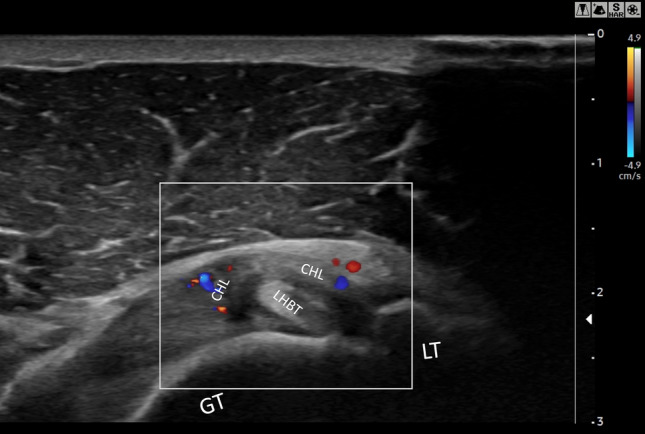

Power Doppler ultrasound

Walmsley et al. in 2013 [30] in a prospective study evaluating the RI of 41 early-stage AC patients documented in 12 (29%) and increased vascularity at PD-US (Fig. 7), confirming the usefulness of detecting an inflammatory pattern in early AC. Subsequently, [17] a case–control study compared Superb Microvascular Imaging® (SMI; Canon Medical Systems, Otawara, Japan) with conventional PD-US in 39 AC patients and 35 healthy subjects displaying a higher sensitivity and specificity in detecting inflammatory flows at the RI for SMI against conventional PD-US (AUC 0,9 vs 0,78 p < 0.01). Furthermore, SMI signal strength was inversely related to shoulder external rotation, ROM, and forward flexion in the AC group (p < 0.05). Five studies documented an increase of vascularization at the RI of patients with frozen shoulder [14, 16, 17, 21, 30]: for a total of 214 patients evaluated, 78 of these (38.44%) displayed an increase in PD-US signal.

Fig. 7.

Directional PD US shows hypervascularity in the RI: axial section of the rotator interval of a right shoulder in a patient with AC. CHL, Coracohumeral ligament; LHBT, Long Head Beceps Tendon; GT, greater tuberosity; LT, lesser tubercle

Power Doppler ultrasound in AC

Despite the nature of AC, which is recognized to start as synovitis and end as fibrosis, few papers evaluated the accuracy of PD-US. Walmsley et al. [30] documented an inflammatory pattern at RI in a subset of patients with early-stage AC. Moreover, those who displayed a positive PD-US signal at RI had a lower duration of symptoms compared to the patients without hypervascular changes. In their cohort of study, they included patients in pre-freezing (0–3 months) and freezing stage (3–9), thus with a heterogenous disease stage; assuming that hypervascular changes at RI are observable only in the early phases of the disease, the group’s heterogeneity could explain the lack of observation of hypervascular signal in most of the examined shoulders. Surprisingly, even if inflammation is held responsible for the pain experienced by patients in early stage AC, Walmsley et al. [30] reported lower pain values for the subjects who displayed a positive PD-US. Subsequently, in a case–control analysis, Kim et al. [17] compared the conventional PD-US with Superb microvascular imaging (SMI®). SMI® is a software that allows the detection of weaker signals compared to conventional PD-US [37]. They reported higher sensitivity and specificity of SMI® than conventional PD-US in detecting slow vascular flows. Moreover, they confirmed CHL thickness and RI hypoechogenicity as useful for AC diagnosis. Although SMI® performance is reported to be higher when compared to PD-US, they reported a good diagnostic accuracy for the latter too. Furthermore, PD-US is an examination that is more accessible in everyday clinical practice in most settings, which makes it easier to be adopted.